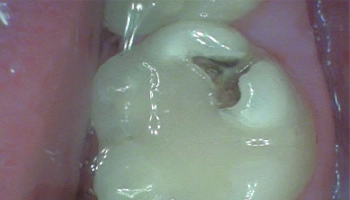

Composite Bonding: Composite Filling

Before and after views of composite bonding on a tooth. After image of a tooth with composite filling restoration.